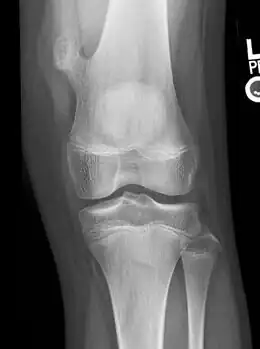

X-ray knee (side view): ossification in the peritendinous tissues in a person with osteochondroma.

Osteochondromas are often asymptomatic and may not cause any kind of discomfort. They are often found accidentally when an X-ray is done for an unrelated reason.[16]

• X-rays are the first tests performed that characterize a lesion. They show a clear picture of dense structures of bones, and will also indicate bone growth pertaining to osteochondroma.[10][16]